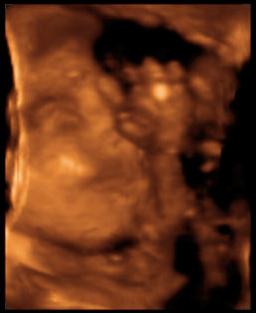

Mindjárt jönnek a 4D képek!!!

Na akkor a 4D képek! Törpike (merthogy neve még változatlanul nincs), fejecskéje 6,71 cm, súlya kb. 920 gr., 1 héttel kisebb mint a kora, így várhatóan augusztus 26-ra leszek újabb időre kiírva, nem aug. 18-ra. Talán a dokim visszaér addigra szabiról, és tudok vele egyezkedni. Szóval összességében jól alakulnak a dolgok. A 4D egyébként irtó jó volt! Most először hallottuk a szívverését is, és nem is tudom szavakba önteni, milyen különös érzés keríti hatalmába az embert ott a félhomályos vizsgálóba, amikor meglátja először a 4D képet. A kezecskéket rendesen, nem csak a csontokat belőle és a halvány körvonalakat. Az orrocskát, a szemecskéjét, még ha csukva volt is, mert a kis drága aludt végig, hiába volt előtte süti meg bármi, nem nagyon hatotta meg :) Az összes kezét, lábát végig az arca előtt tartotta szinte teljesen eltakarva azt, de azért lehetett látni is, na meg olvadozni. Egyébként medence fekvésű jelenleg, vagyis hát a vizsgálatkor, de van még bőven ideje, helye befordulni és mocorogni, úgyhogy nem aggódom. Kértem a dokit, hogy nézze meg a méhlepény-méhszáj távolságát. Kérdezte, mert hogy mélyen volt a lepény? Mondom igen, 12 mm-re. Megmérte, és képzeljétek, a távolság 6!!!!! cm-re nőtt, tehát teljesen felhúzódott, illetve nem kicsit, és már azt is írta a leletre hogy hátsó fali korban érett placenta :) Június 13-án megyek 30 hetes UH-ra a dokimhoz, majd kérem őt is hogy mérje meg, kíváncsi vagyok igazolja-e ezt, és hogy akkor nincs akadálya (legalábbis emiatt) a spontán szülésnek.

Férjecském majdnem elsírta magát a meghatottságtól a vizsgálat elején még (ezt utána mondta), és egyébként azóta is 10 centivel közlekedik a föld fölött, láthatóan eufórikus állapotban van, ami szűnni nem akar, nagyon imádnivaló :) Mondjuk ha a másik nem lenne, akkor ugyanez, de igaziból más most a kapcsolat, én is így érzem. Személyesebb lett a baba iránti szeretetünk, és amikor mentünk az UH után az utcán, olyan más volt. Mintha kivilágosodott volna minden, pedig viharos esős idő volt, és az emberek is mások lettek volna, én nem is tudom, nagyon jó érzés volt :)

Jól van, nem csigázom tovább a kíváncsiságotokat. Szerintem nem kell hozzá magyarázat, magatoktól is látni fogjátok a lényeget ;)

Ásítós Törpike :)